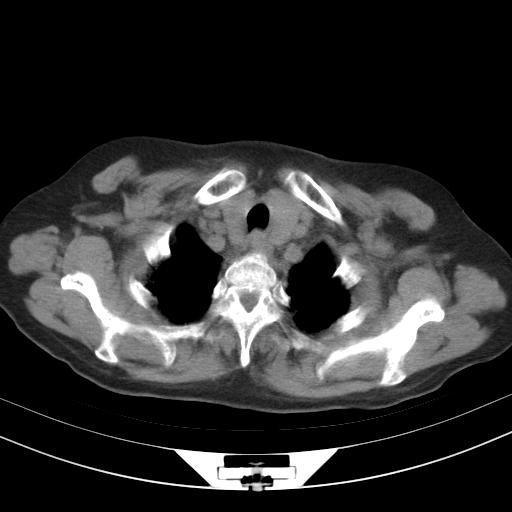

老年女性,嗜睡3天,意识模糊。轻咳,无发热。

两肺慢支炎伴感染,左侧胸腔积液。纵膈及双侧肺门淋巴结肿大建议复查。

1)两肺感染性病变;建议抗炎治疗后复查。2)纵隔淋巴结肿大。3)左侧胸腔积液。